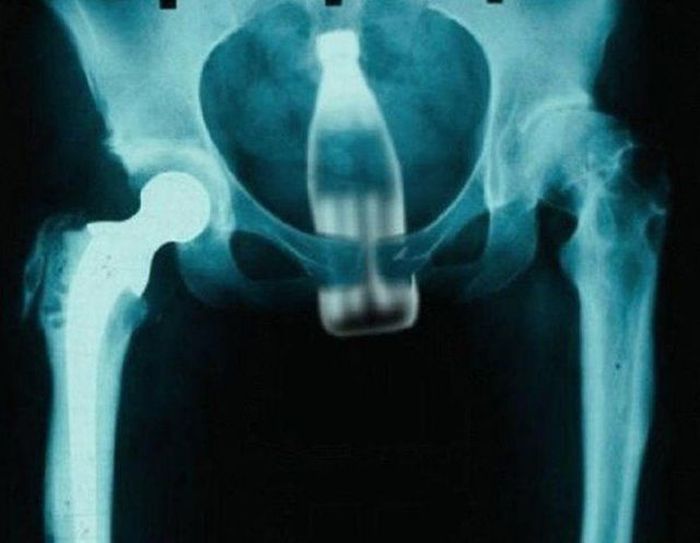

Ou comme ça, ça peut marcher aussi.

Je veux même pas savoir comment il a faits.

Ben par le coté pointu ça rentre mieux.

Ca doit être drôle de le retirer si avec la capsule